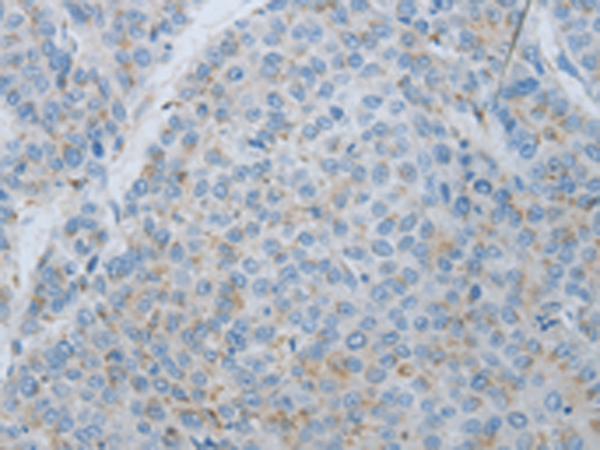

分类: 科研抗体货号: P11008别名:应用: IHC反应种属: Human

分类: 科研抗体货号: P11007别名: LSFC, GP130, LRP130, CLONE-23970应用: IHC反应种属: Human, Mouse, Rat

分类: 科研抗体货号: P11006别名: ADCAD2应用: IHC反应种属: Human, Mouse

分类: 科研抗体货号: P11046别名: FRAP, FRAP1, FRAP2, RAFT1, RAPT1应用: IHC反应种属: Human, Mouse, Rat